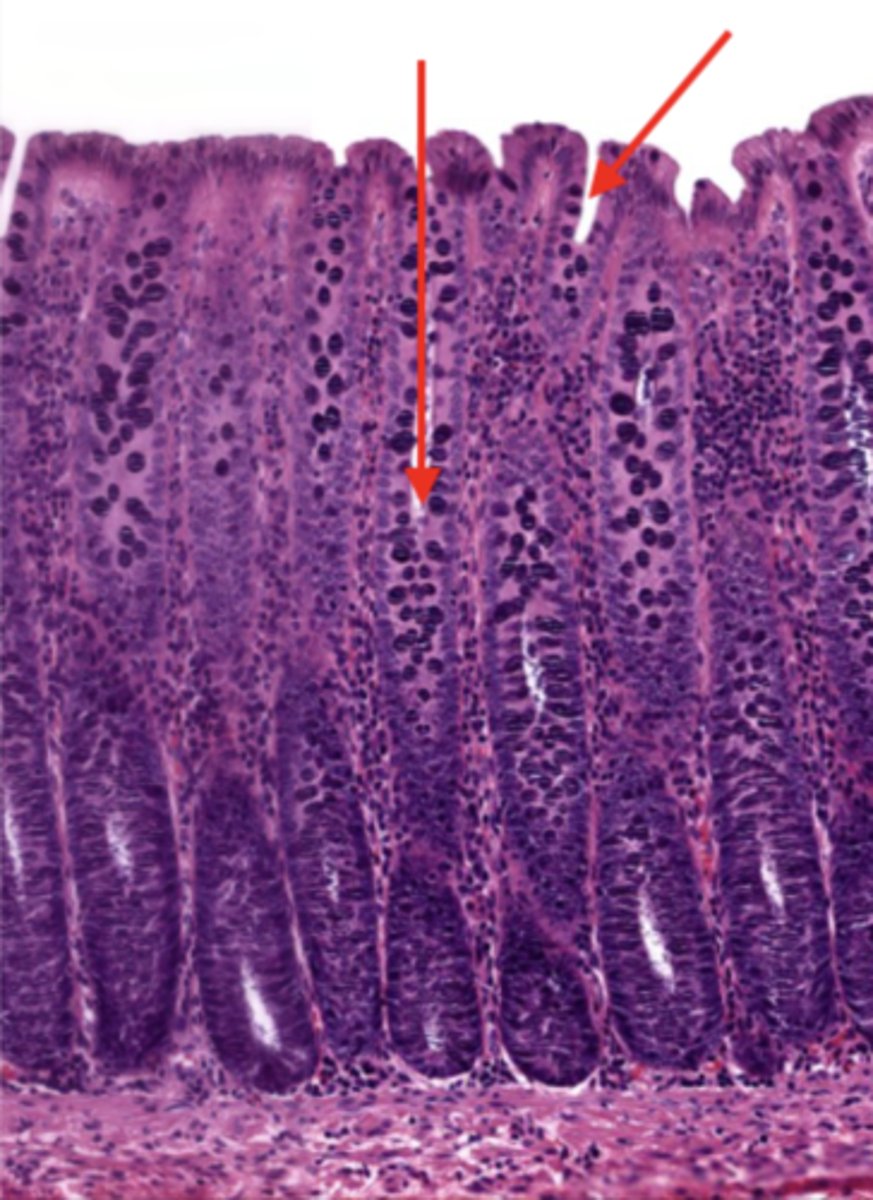

colon (histology)

simple columnar epithelium

what kind of epithelium lines the mucosa of the colon?

intestinal glands/crypts (colon)

lumen (colon)

mucosa (colon)

mucosal epithelium (colon)

lamina propria (colon)

muscularis mucosa (colon)

submucosa (colon)

contains glands and blood supply

muscularis externa (colon)

serosa/adventitia (colon)